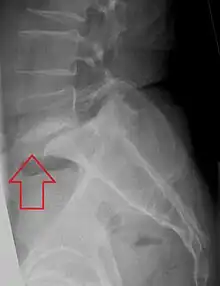

| X-ray of the lateral lumbar spine with a grade III anterolisthesis at the L5-S1 level | |

Spondylolisthesis is the displacement of one spinal vertebra compared to another. While some medical dictionaries define spondylolisthesis specifically as the forward or anterior displacement of a vertebra over the vertebra inferior to it (or the sacrum),[1][2] it is often defined in medical textbooks as displacement in any direction.[3][4] Spondylolisthesis is graded based upon the degree of slippage of one vertebral body relative to the subsequent adjacent vertebral body.[5] Spondylolisthesis is classified as one of the six major etiologies: degenerative, traumatic, dysplastic, isthmic, pathologic, or post-surgical.[6] Spondylolisthesis most commonly occurs in the lumbar spine, primarily at the L5-S1 level, with the L5 vertebral body anteriorly translating over the S1 vertebral body.[6]

Olisthesis (synonym olisthy) is a term that more explicitly denotes displacement in any direction.[7] Forward or anterior displacement can specifically be called anterolisthesis.[3][4] Anterolisthesis commonly involves the fifth lumbar vertebra.[8] Backward displacement is called retrolisthesis. Lateral displacement is called lateral listhesis[3] or laterolisthesis.[4]